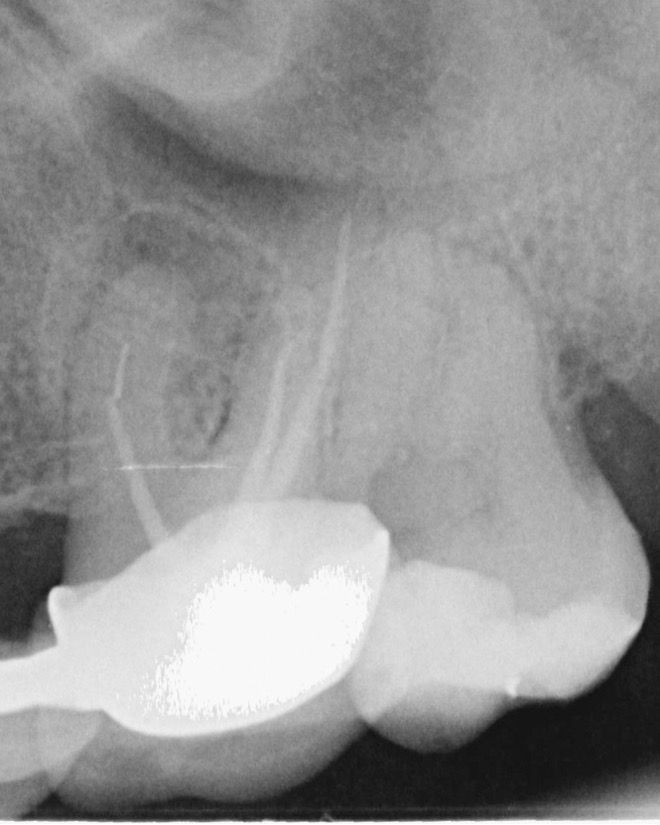

Kontrolden 14 ay sonra (2025 Nisan) hastamız bu sefer 26 numaralı dişinde ağrı şikayeti ile kliniğimize başvurdu İlgili dişe sonunda retreatmant tedavisine başlanabildi. (Şekil 4).

(Şekil 4) 2025 Nisan meziobukkal kök ucunda daha da genişlemiş periapikal lezyon